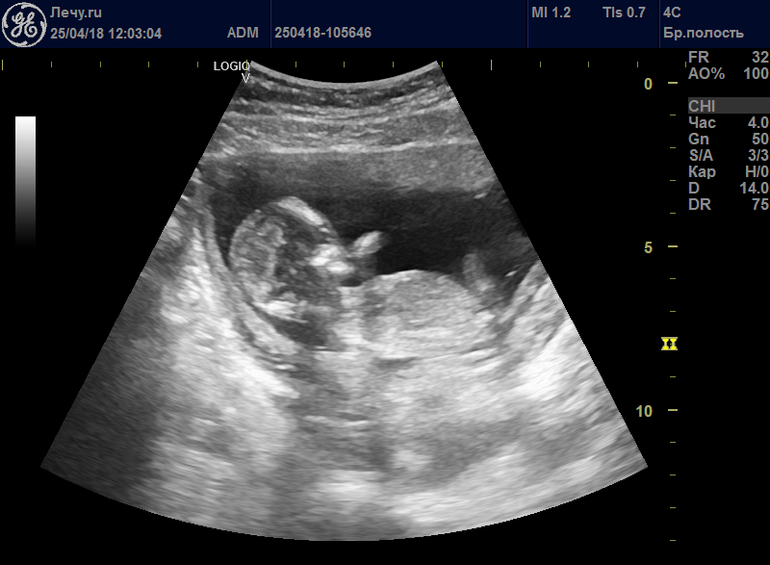

Девочкиии!!!!У нас будет второй пацааан!!!!!!УРАААААААААА😊🎈🎈🎈🎈🎈

Пол малыша

И узист меня очень обрадовал!!! Будет второй пацан😈 Не описать, как я рада😝😝😝 Первый мальчишка тоже) Разница 2,8 Это крутоо, это слишком круто💕💕💕😊 Надеюсь очень, на втором скрининге, яички не пропадут🎈🎈🎈🎈🎈